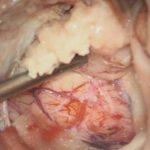

No.’25_97 手術前1

No.’25_97 手術前2

No.’25_97 摘出 前

No.’25_97  摘出 中

髄膜腫

頭蓋内腫瘍摘出術